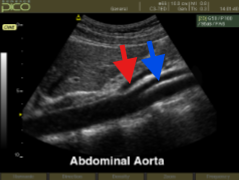

What structure is seen at the red arrow?

What structure is seen at the blue arrow?

Celiac artery

SMA